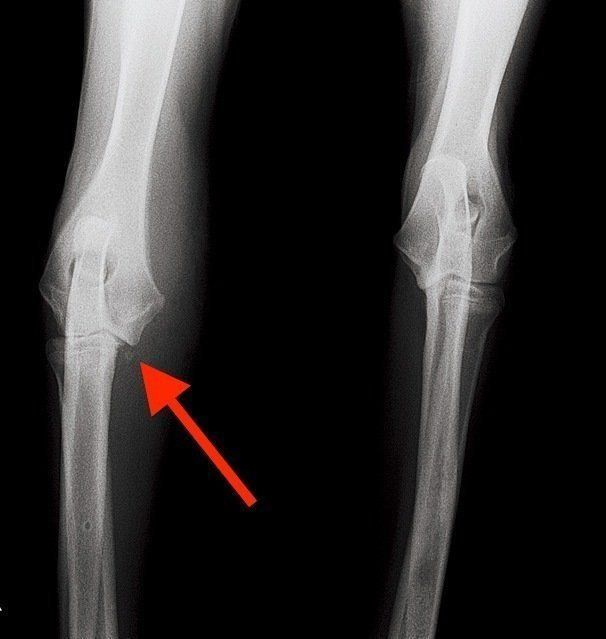

肘関節形成不全(ちゅうかんせつけいせいふぜん)は、前足首とひじの間にある2つの骨の成長の不均衡により、肘関節の痛みと変形を起こす病気です。

そもそも犬の前足には体重の多くがかかるのに、後ろ足のひざのようなクッション機能がなく、ひじを痛めやすい傾向が。大型犬に多い病気ですが中型犬もなり、前足を引きずったり、前足を上げたりします。生後4カ月までに見つかれば進行を抑える手術をすることも。

内側鉤状突起(ないそくこううじょうとっき)という肘関節の一部が壊れた例。骨の破片が確認できる